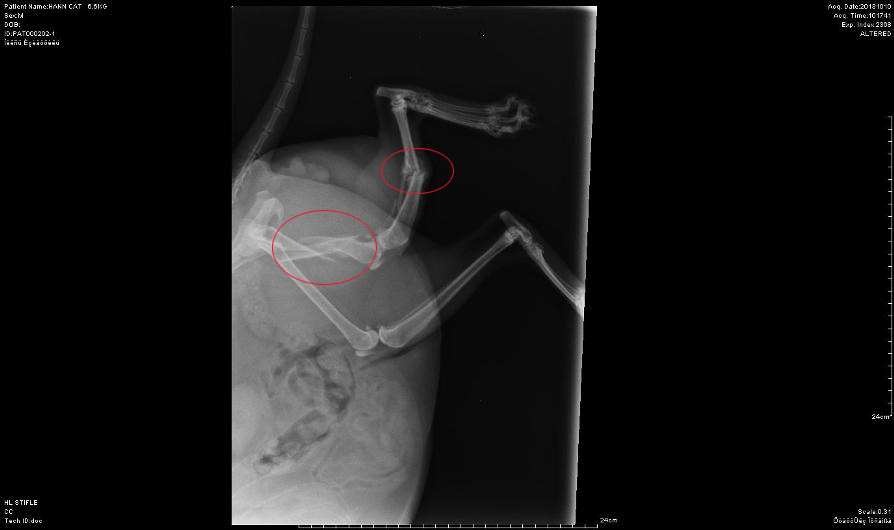

Also stellte man das Katerlie

für ein paar Wochen ruhig, in der Hoffnung, dass es doch irgendwie

von alleine ausheilen würde, leider war das nicht der Fall, wie die

Röntgenbilder 4 Wochen später zeigten, zudem humpelt Shakespeare

immer noch sehr stark und kann das Bein nicht belasten.